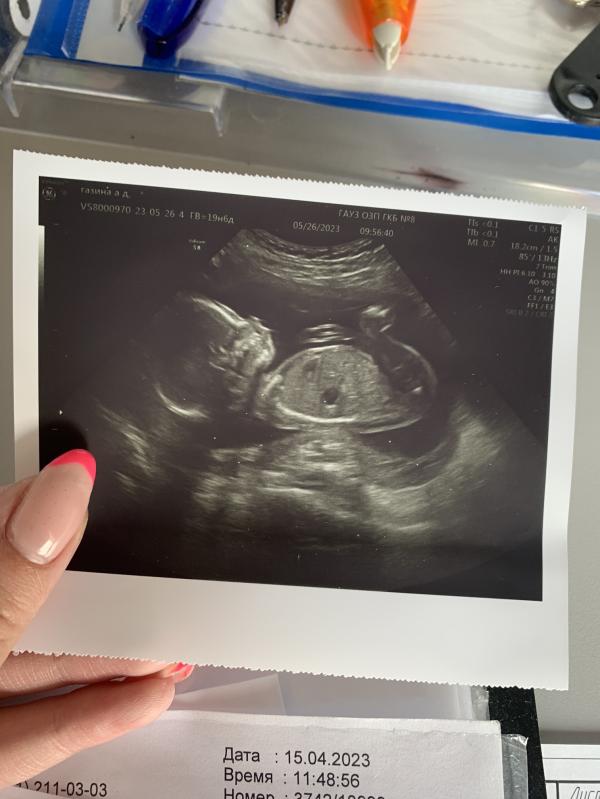

Сегодня был долгожданный 2-й скрининг и мы увиделись с малышом 😻. Все хорошо и растём как надо.